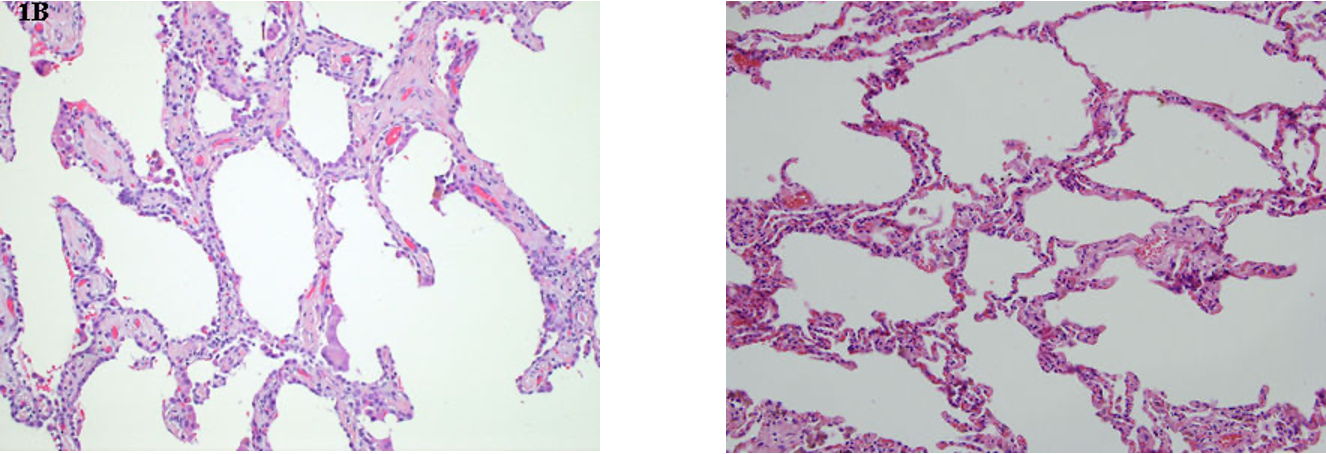

How does BRSV present histologically?

Thickened alveoli septae by lymphocytes and mononuclear cells

^^ normal on L, R = tissue between alveoli infected w/ RSV -> inflam cells, MNGCs -> difficult exchange of gas across thicker surface

^^ alveolar wall thickening on L, normal on R